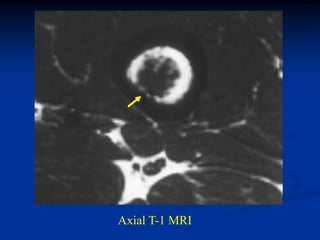

Case #556

55 year male with

enchondroma tibia

Axial T-1 MRI

tumor